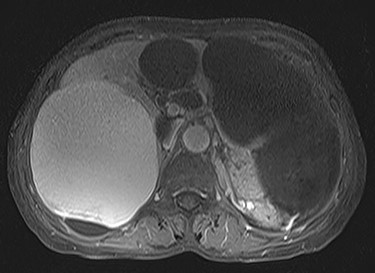

A 74-year-old woman presented with right upper abdominal pain and poor dietary intake. She had no notable medical history or history of abdominal trauma. Abdominal computed tomography (CT) showed multiple liver cysts, with the size of the largest cyst in the right lobe measuring 155 × 113 × 106 mm (Fig. 1a). In addition, a large cyst measuring 135 mm in the left lateral lobe strongly compressed the stomach (Fig. 1b). T1-weighted magnetic resonance imaging revealed different findings in the right and left lobe cysts, and there were no enhanced structures in the liver cysts (Fig. 2). Positron emission tomography-CT did not show increased 18F-fluorodeoxyglucose metabolism in any of the liver cysts (Fig. 3). Moreover, hepatobiliary scintigraphy with CT showed no biliary communication with the liver cysts (Fig. 4). The patient was diagnosed with symptomatic and multiple liver cysts with no biliary communication or malignancy. Therefore, LF was performed.

Preoperative T1-weighted magnetic resonance imaging showing different findings in the right and left lobe cysts.